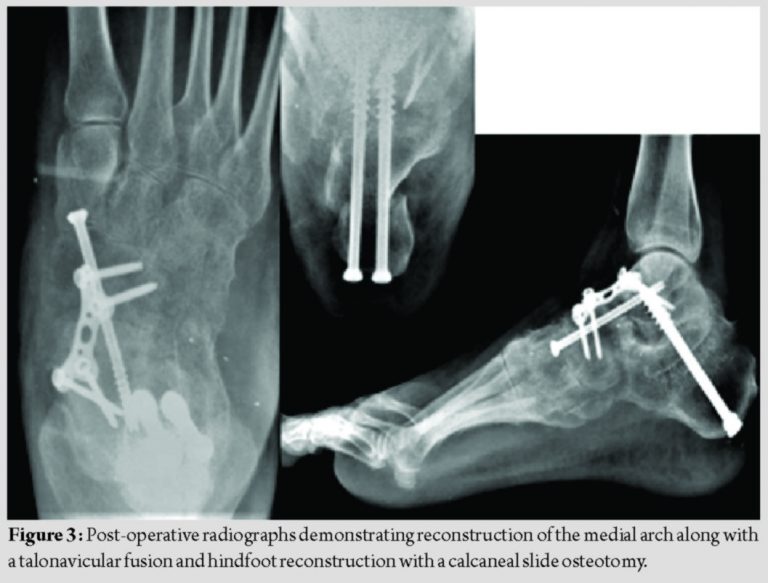

Given her disablement and failure of conservative modalities over the past 2years, a decision of surgical management was undertaken. Her pre-surgery American Orthopedic Foot and Ankle Society (AOFAS) score was 35. Correction of heel valgus with a sliding medial calcaneal osteotomy, release of Achilles tightness with gastrocnemius recession, and correction of a collapsed medial longitudinal arch with a corrective fusion of talonavicular joint was planned. In a floppy lateral position, a gastrocnemius recession was performed followed by a medial displacement calcaneal osteotomy.

The osteotomy was fixed with two 6.5 mm cannulated cancellous screws, pushed through the subtalar joint up to the neck of the talus. Finally, to correct the sag at the talonavicular joint, a dorsal open wedge osteotomy was carried out at the level of the talonavicular joint, packed with iliac crest bone graft and fixed using a plate, and screws to restore the medial arch (Fig. 3).